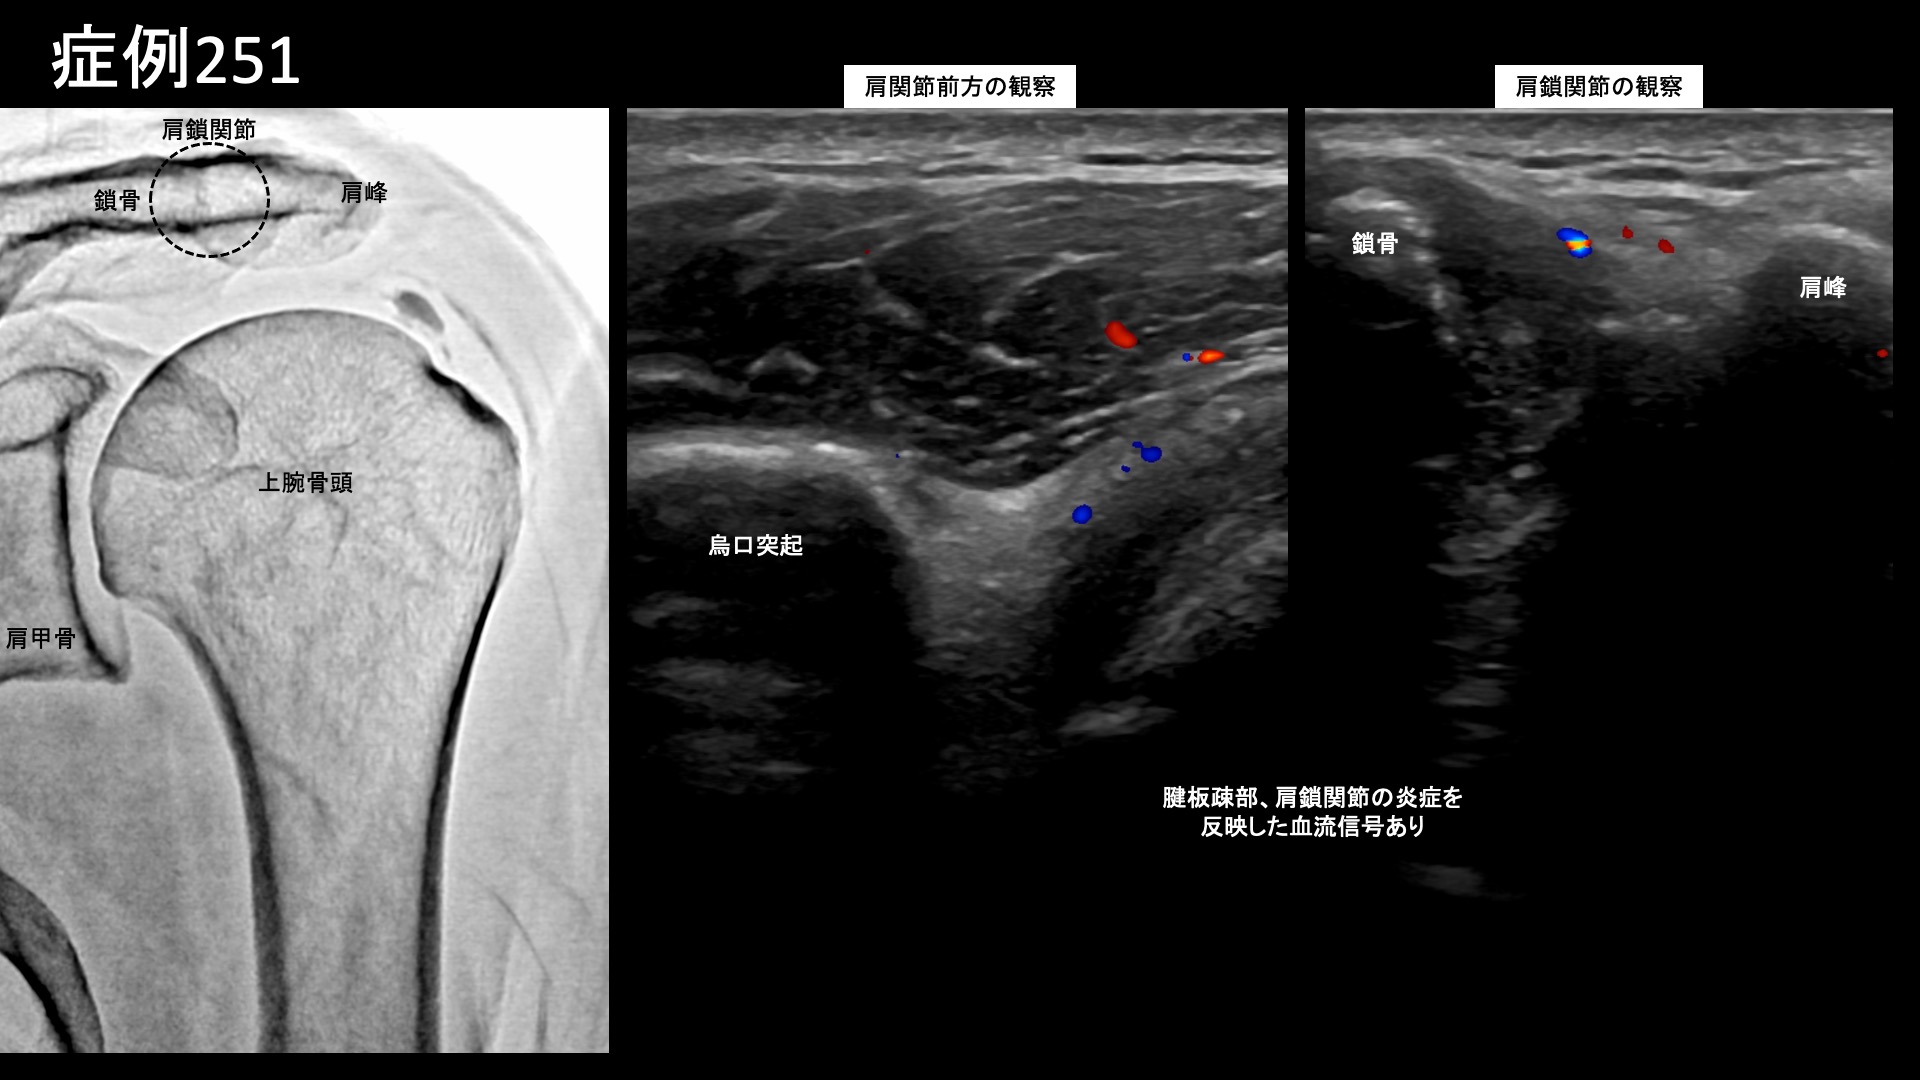

肩:肩こり・四十肩・五十肩 【50代:男性】最初からここに来ればよかった・・ステロイド注射無効で半年間苦しんだ石灰沈着性腱板炎による肩の痛み(石灰沈着性腱板炎、肩関節周囲炎) 2025.11.26 鴨井院長による動画解説 受診までの経過 半年前から左肩が痛むようになり、整骨院や整形外科に通っていました。鎮痛薬内服のほか、ステロイド注射も複数回受けましたが、効果は感じられず、酷くなるばかりでした。腕が挙げられなくなり、ついには夜間痛まで生じるようになりました。当院の治療を知り受診されました。 診察時の所見 腕は水平までも挙がらない状態でした(外転80度)。レントゲンでは腱板領域に石灰を認め、エコー検査では同部位に一致した腱板石灰沈着を認めたほか、周囲に炎症による(モヤモヤ血管を反映した)異常血流信号を認めました。更に、腱板疎部領域や肩鎖関節においても同様に炎症所見を認めました。石灰沈着性腱板炎による肩関節周囲炎の診断です。治療適応と判断し、モヤモヤ血管(病的新生血管)に対する運動器カテーテル治療(微細動脈塞栓術)を受けていただきました。 治療の所見 血管造影を行うと、胸肩峰動脈、前上腕回旋動脈、肩甲下筋枝などでモヤモヤ血管が濃染像として描出されました。特に肩甲上動脈では強い濃染像を認めました。血管造影所見を比べると、石灰沈着性腱板炎では、このように五十肩(凍結肩)よりも強い炎症であることが多いです。ステロイド注射が効かなかったというのも頷けます。いずれも治療後モヤモヤ血管は画像上速やかに消失しました。その他複数箇所の治療を行い終了しました。 治療前画像:損傷を受ける、あるいは繰り返しのストレスにより発生した異常な新生血管 治療後画像:カテーテルを用いて塞栓物質を血管内に投与し新生血管を塞いだ状態 治療費用:治療する部位によって費用が異なりますのでこちらをご参照ください。 主なリスク・副作用等:針を刺した場所が出血により腫れや痛みを生じたり、感染したりすることがあります(穿刺部合併症)。造影剤によるアレルギー(皮膚のかゆみ・赤み・息苦しくなるなどの症状)が出ることがあります。 治療後の経過 治療翌日から改善しました。治療後3週間では、ほとんどの痛みが無くなりました。肩関節の可動域も完全に回復し、バンザイもできるようになりました。半年間苦しんでいた痛みのあまりの回復ぶりに、『最初からここに来ればよかった』と話されるほどでした。エコーで確認すると、まだ石灰沈着については大きな変化はありませんでしたが、今後吸収されていくことも期待できます。非常に経過良好であったことから、終診となりました。石灰沈着性腱板炎は強い炎症を伴っていることが多く、その苦痛も五十肩以上になることが少なくありません。カテーテル治療は強い炎症にこそ、強い効果を発揮します。実際に、本症例では非常に早期から快復しました。罹病期間が長くなければ、石灰も吸収されて無くなります。 非常に良い適応疾患の一つですので、お悩みの方はぜひご検討いただくと良いと思います。 石灰沈着性腱板炎の詳細 【60代:女性】尿が溜まると膣が痛い!夜も寝られず。繰り返す膀胱炎から発症した間質性膀胱炎および膣前庭炎に対するモヤモヤ血管カテーテル治療(間質性膀胱炎、膣前庭炎) 前の記事 【70代:男性】急激に悪化した膝の痛みで歩けなくなり夜も寝られず水も溜まる・・ネフローゼ症候群を合併した変形性膝関節症の実例(変形性膝関節症、ネフローゼ症候群) 次の記事